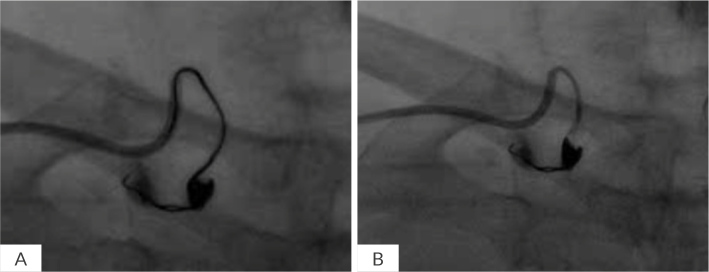

Case description: This report highlights three cases of perforated artery managed with coil embolization. The first case involved perforation of a small branch of the internal mammary artery, the second a ruptured aneurysm in the superior mesenteric artery and the third a distal branch perforation of the diagonal artery. All patients presented with significant haemorrhage, requiring urgent intervention. Coil embolization was successfully performed in all cases, achieving haemostasis and preventing further complications.